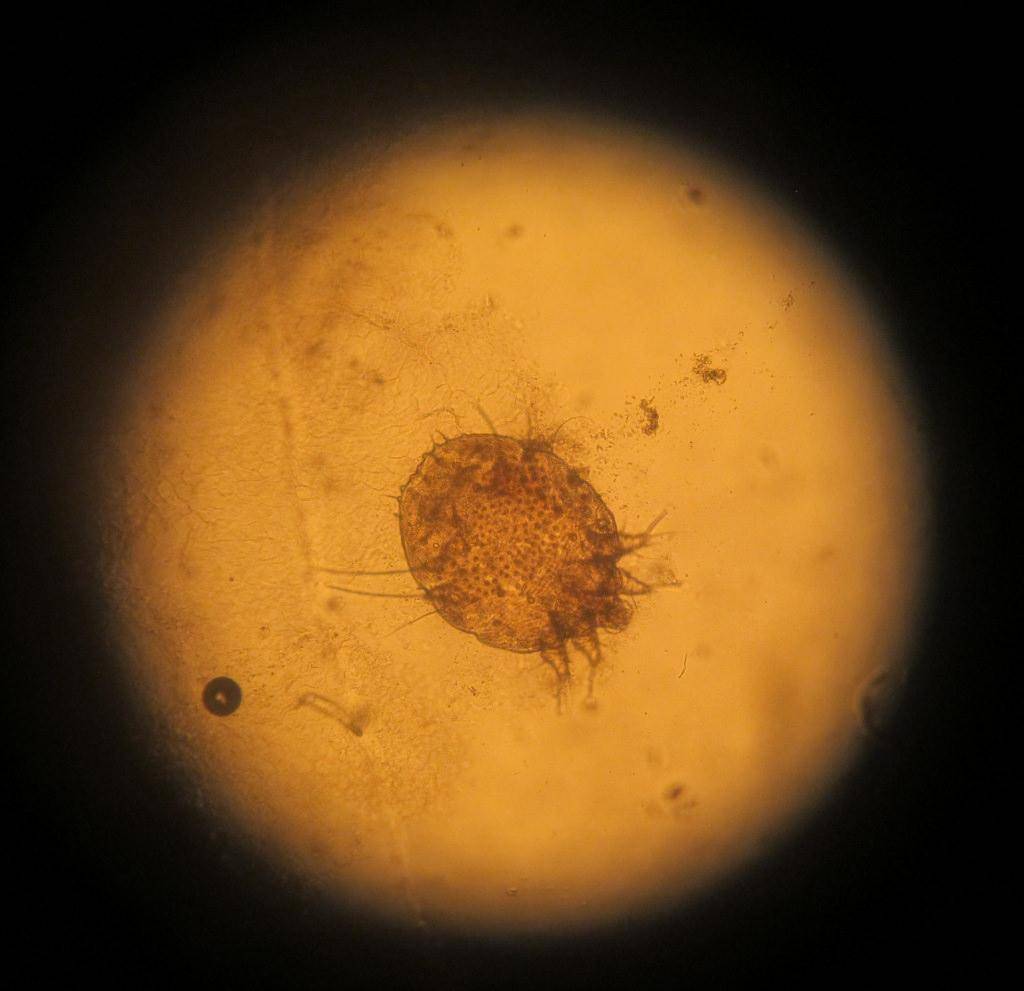

Причина появления поражений – паразит Sarcoptes scabiei. Переносить его может любое живое существо, которое подверглось заражению. И чем больше поражений на теле больного, тем выше риск, что он может кого-то заразить.

как выглядит чесоточный клещ

Заражение осуществляют самки и личинки. Самка обитает в коже. В дневное время она неактивна, но вечером она активно прогрызает ходы, размножается, питается и выделяет продукты переработки. Следовательно, самый большой риск заразиться появляется именно в вечернее-ночное время, когда клещ проявляет большую активность.

Для определения наличия кожных паразитов, у животного берут несколько соскобов кожи. Различные поражения кожного покрова могут вызвать клещи вида Cheyletiella.